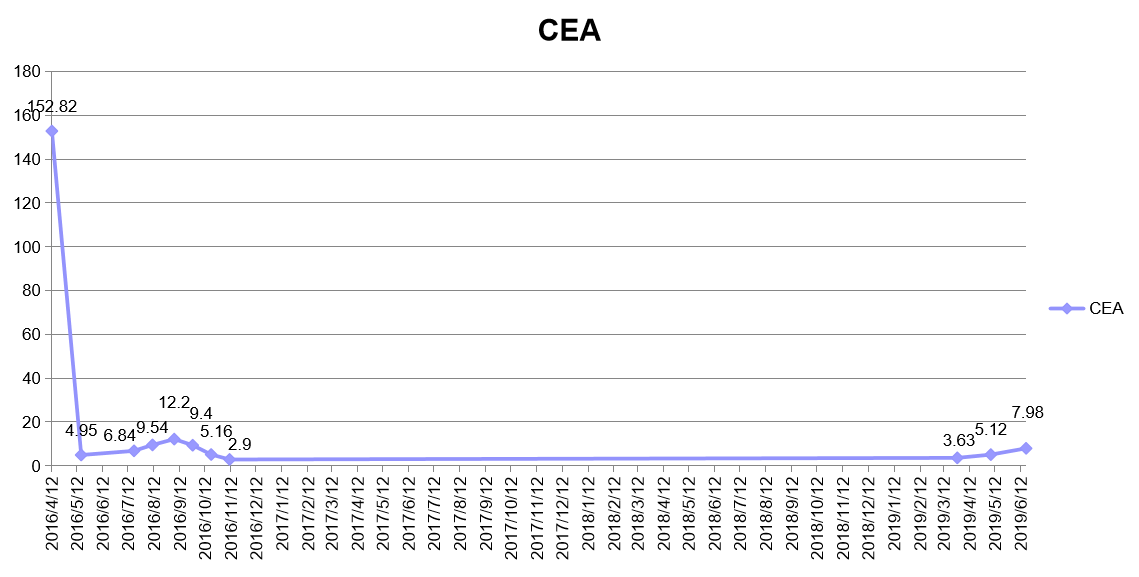

肿瘤标志物:

因不良反应停用贝伐珠单抗后单药口服维持化疗,肿瘤标志物仍然长久控制在正常范围